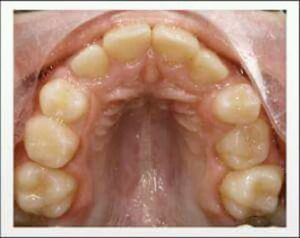

Spot this and what is d/d ?

High arched palate right??

DD- Marfan's syndrome... Down's syndrome... Adenoid hyperplasia

It is a picture of high arched palate